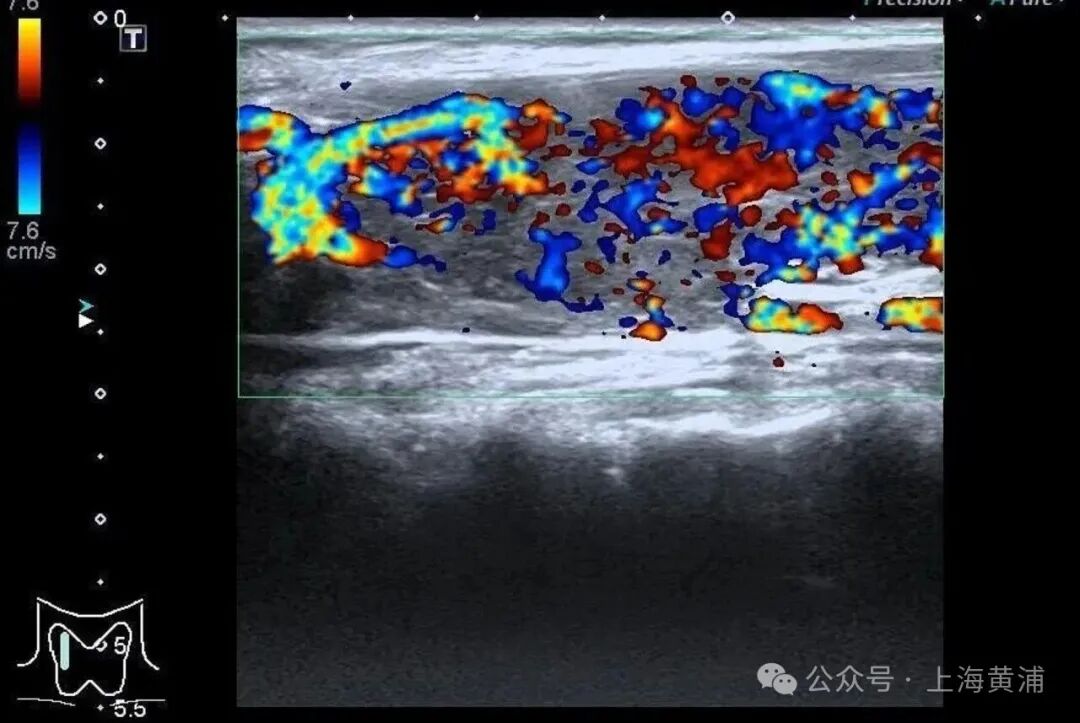

{jz:field.toptypename/}甲状腺功能查验中,游离T3高达20.83 pmol/L(正常值3.5 - 6.5pmol/L),游离T4高达88.42 pmol/L(正常值11.5 - 22.7pmol/L),这两项中枢激素都杰出正常上限数倍,而本应调控它们的促甲状腺激素(TSH)却险些测不出来,这明确说明了陈女士患有极其严重的甲状腺毒症。腹黑超声终结通常笼罩乐不雅,射血分数仅有40%(正常应高于55%),这意味着腹黑泵血才略大幅着落。

同期,CT查验发现她的双侧胸腔、腹腔存在积液。抽象各项查验终结,医师判断陈女士患上了甲状腺危象,这是甲亢最不吉的并发症。